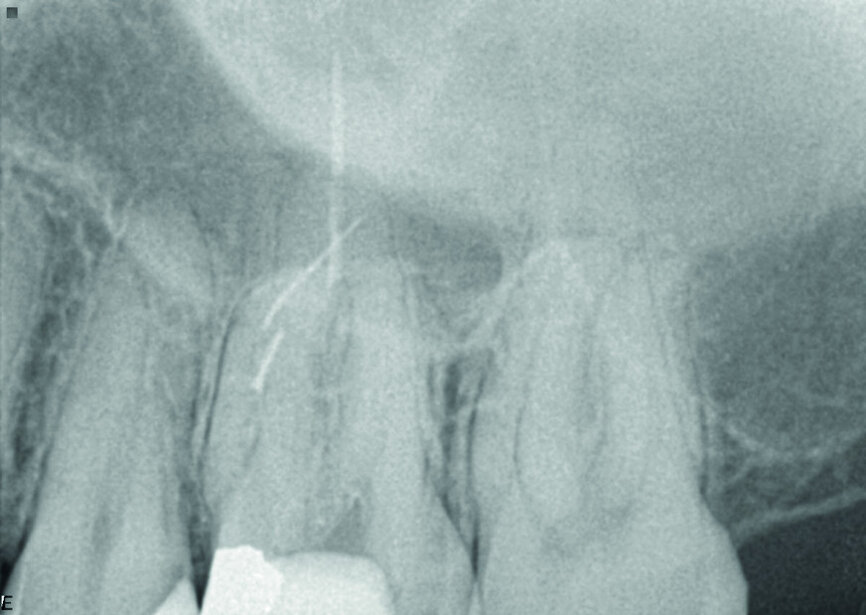

The patient was referred for a dull pain affecting a maxillary molar. On the preoperative radiograph, we could see a diversity of obturation materials, including single cones, resin cement and silver cones, with some of them already fragmented and one piece protruding from the root. Looking closely at the sinus and the sinus membrane, we could see that the membrane had been perforated by the inflammatory/infection process, which had led to sinus infection (Fig. 15).

Under the operating microscope and using ultrasonic and K3XF rotary files (Kerr Dental), I managed to clear the root system of all the previous obturation materials, and placed a dry cotton pellet and temporary cement, as the patient had become tired during this long appointment (Fig. 16). Figure 17 shows some minor debris of silver cones that had passed beyond the mesial apex and using the MacroCannula of the EndoVac, I managed to retrieve one small piece of the silver cone and to complete the chemical cleaning of the root canal system.

Figure 18 shows the immediate postoperative situation, focusing on the obturation of the mesial canals, and a slight improvement of the membrane and the sinus is evident. Figure 19 shows the three-month follow-up with an almost complete closure of the membrane and the bone of the sinus floor.